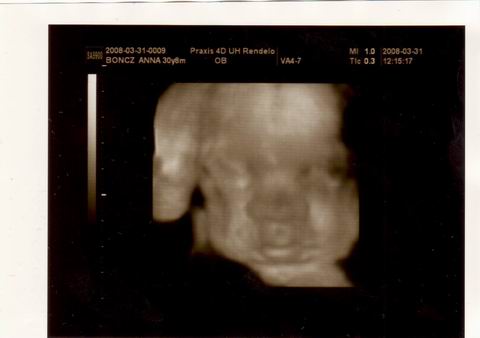

Mink volnánk [img]